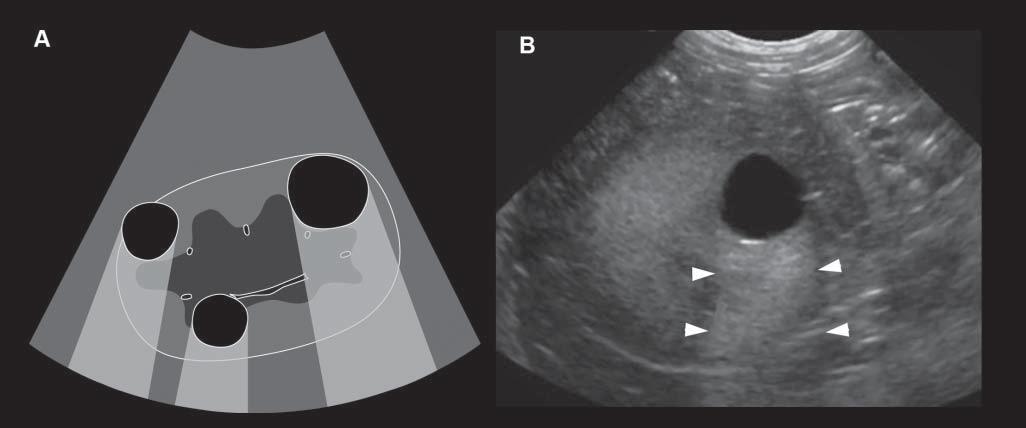

AcousticEnhancementorIncreased Through-transmission

Conversely,wavesencounteringastructurethatallows themtopassthroughmoreeasily(poorlyattenuating), suchasaliquid-filledcyst,remainofhigherintensity whenreachingthedeepertissues,allowingechoesof greaterstrengthtoreturntotheprobe.Consequently, thesedeepertissuespresentanartifactualincreasein echogenicity(Figure1.15).Acousticenhancementis typicallyrecognizeddeeptoafluid-filledstructureina softtissuebackground,suchasdeeptothegallbladder ortoalivercyst,makingthemeasytoidentifyand

Figure1.15. Enhancement.A: Thisartifactisrepresentedbyazoneofincreasedechogenicity,behindafluid-filledstructure.Onthisschematicdrawing,severalrenalcystsareseenassociatedwithdistalenhancement B: Anexampleofasimilar cystispresentinthisdog,whereitisseenasarounded,well-definedanechoicrenalcystassociatedwithfarenhancement (arrowheads).

distinguishfromsolidlesions.Tissuesdeeptothe urinarybladderandorgansfloatinginascitesoften becomehyperechoic.